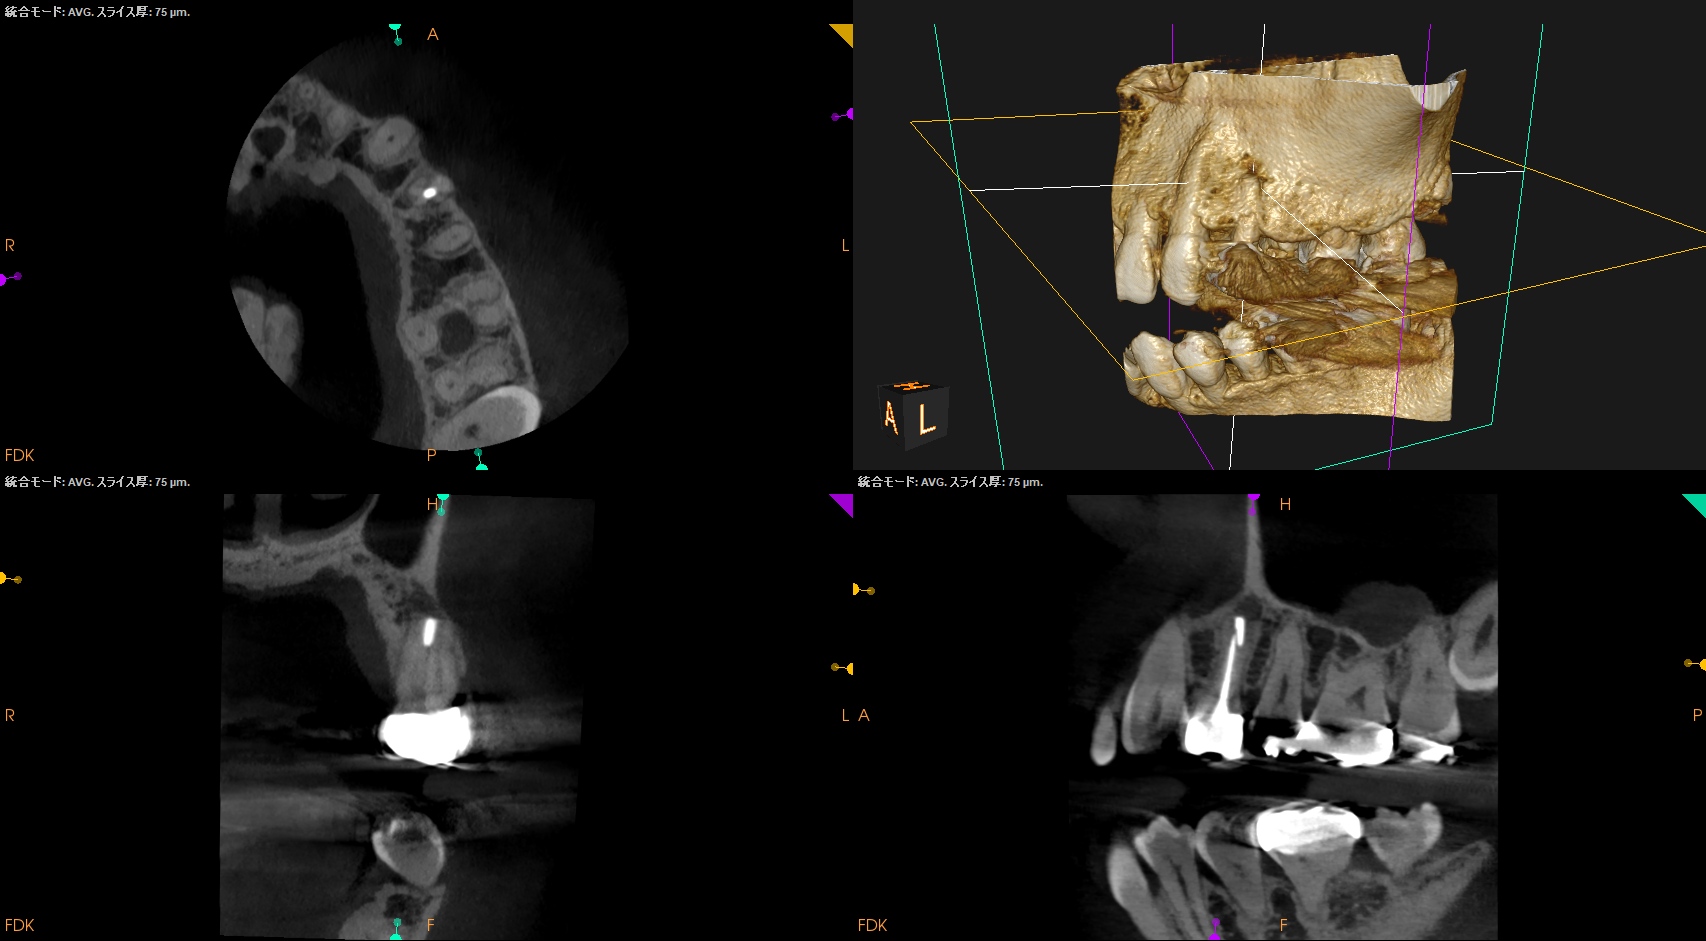

#12 Apicoectomy(2025.3.7)

Apexの位置のOsteotomyすると、そのApexは容易に発見できた。

根尖を3mm切断し、メチレンブルーで染色した。

問題はない。

逆根管形成し、逆根管充填した。

ペントロンジャパンの

エンドセム MTA クイックペースト R

で逆根管充填した。

いわゆるシーラー逆根管充填(そんな言葉があるのか?)である。

術後にPA, CBCTを撮影した。

縫合して終了した。

#12 Apicoectomy 1yr recall(2026.2.27)

1年前と比較した。

問題は解決した。